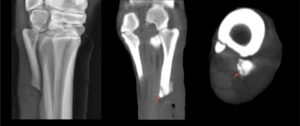

Axial fracture of proximal MTIV of right rear limb of a 2yr-old Quarter horse; undetectable by radiograph.

Standing CT technology has changed the face of screening and diagnostics in equine medicine. Safe, quick, high-quality scans have made this modality an accessible and effective tool for diagnosing pathology that cannot be detected on radiographs (image 1). The Asto CT Equina® scanner is currently being used by Racing Victoria in Australia to screen all horses entered into the Melbourne Cup, prior to them running to assist in early detection of potentially catastrophic injuries.